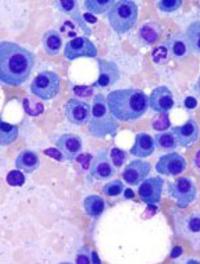

Le pronostic du myélome multiple s’est amélioré avec l’arrivée sur le marché des inhibiteurs du protéasome et les immunomodulateurs. [...]

L’association méphalan+prednisone (MP) a longtemps été le traitement de première ligne chez les patients âgés atteints de myélome multiple [...]